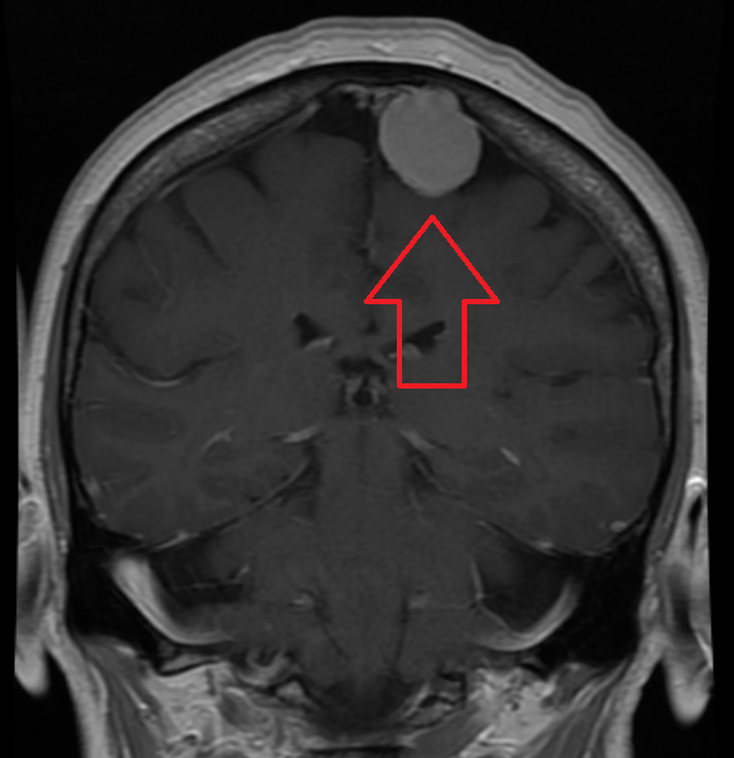

A Meningioma is a Tumor that arises from the meninges — the membranes that surround your brain and spinal cord. Most Meningiomas are noncancerous (benign), though rarely a Meningioma may be Cancerous (malignant). Some Meningiomas are classified as atypical, meaning they're neither benign nor malignant but, rather, something in between. A Meningioma doesn't always require immediate treatment. A Meningioma that causes no significant signs and symptoms may be monitored over time. Signs and symptoms of a Meningioma typically begin gradually and may be very subtle at first. Depending on where in the brain or, rarely, spine the Tumor is situated, signs and symptoms may include: Changes in vision, such as seeing double or blurriness Headaches that worsen with time Hearing loss Memory loss Loss of smell Seizures Weakness in your arms or legs